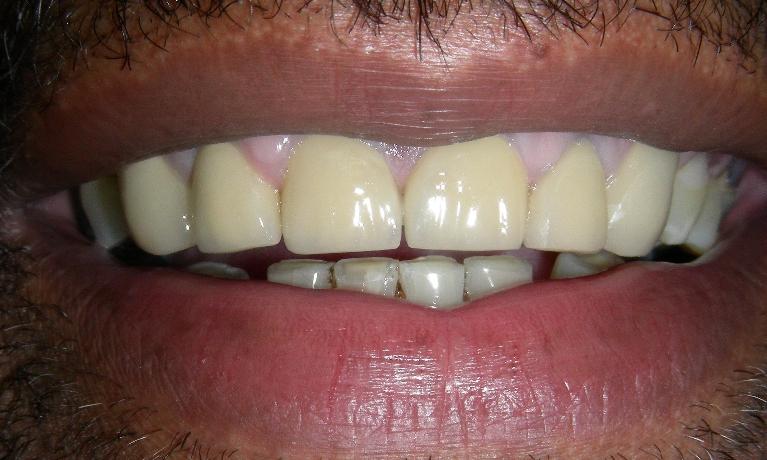

Before

After

Porcelain Veneers

These porcelain veneers replaced the ones the patient had received several years earlier.